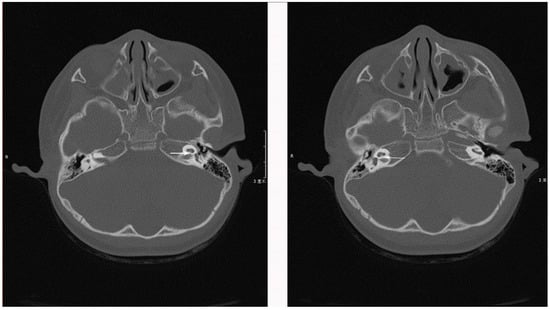

1.1. Case 1

1.2. Case 2